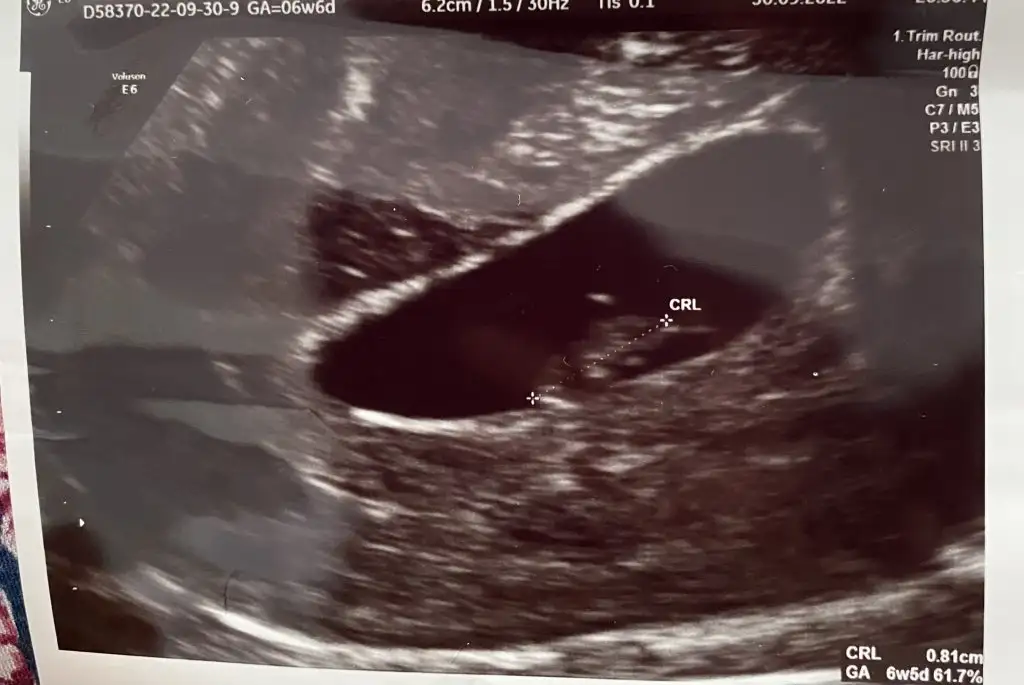

Selam.12+4 karından ultrason.tahminin nedir merak ettim doğrusu 😍

• C2925E76-C64C-4826-AD97-FDA759DF7154.webp

C2925E76-C64C-4826-AD97-FDA759DF7154.webp

31,6 KB · Görüntüleme: 77